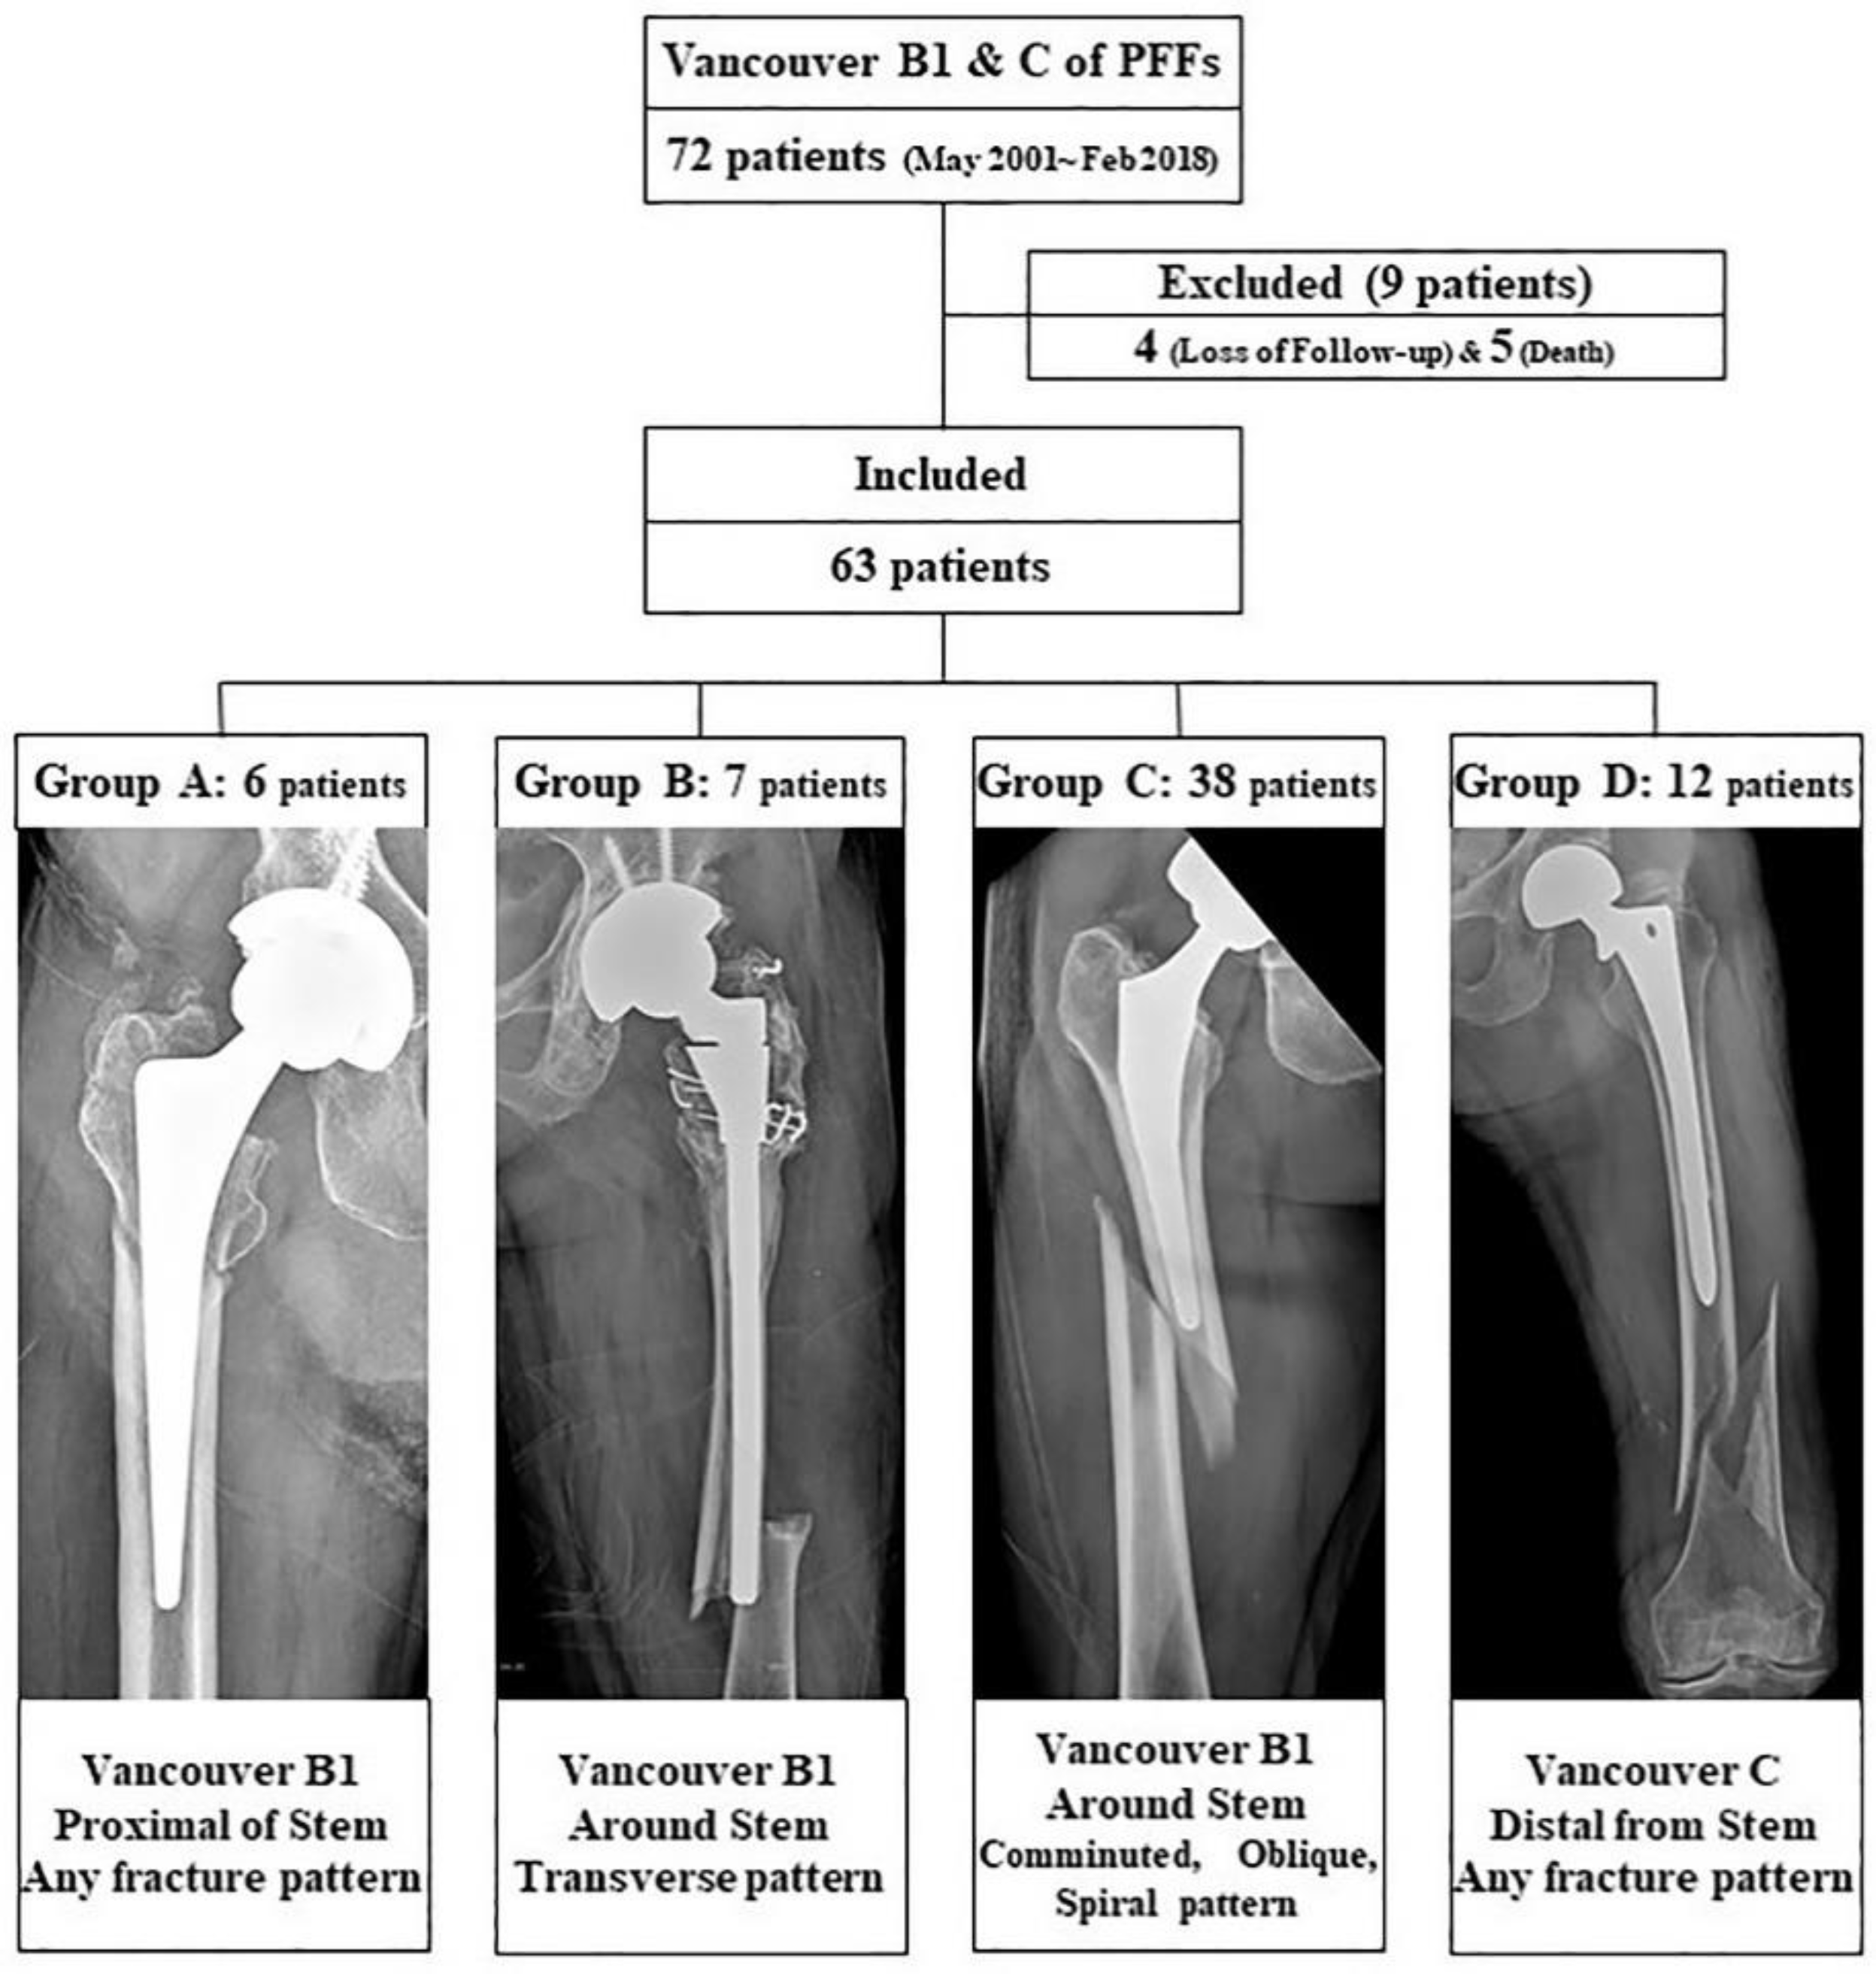

We retrospectively identified a consecutive series of 72 patients with Vancouver type B1 and C PFFs treated with LCP between May 2001 and February 2018. Only patients with fracture fixation with an LCP (Synthes, Paoli, PA) without supplemental allograft struts or dual plate fixation were included in the study. Intraoperative PFFs and atypical fracture patterns were excluded. We followed these patients up at scheduled visits to evaluate radiographic and clinical outcomes. Of the 72 patients considered for this study, four patients were lost to follow-up monitoring before the end of the minimum one-year follow-up period, and five patients died due to unrelated reasons. Finally, 63 patients were enrolled in the study (

Figure 1).

The PFFs were classified according to the Vancouver classification system [

9,

10]. Vancouver B1 fractures were subdivided according to location, fractures of the proximal part of the stem, and fractures around the tip of the stem. We defined the fractures around the tip as those cases with the primary fracture line passing the tip of the stem. Classification of the fractures according to the fracture pattern were as follows: oblique, spiral, transverse, and comminuted fractures. We identified six periprosthetic fractures of proximal Vancouver B1 fractures (Group A). Vancouver B1 fractures around the stem tip were grouped into seven transverse fracture patterns (Group B) and 38 other fracture patterns, such as comminuted, oblique, or spiral (Group C). Vancouver C fractures consisted of 12 periprosthetic fractures with spiral, comminuted, or oblique patterns (Group D) (

Figure 1). Of these 63 patients, 36 and 27 were male and female, respectively. The mean age was 67.6 years (range: 32–91 years) and the mean body mass index was 22.1 (range: 15.6–32.0) at the time of surgery. The mean follow-up period was 47 months (range: 12.0–168 months). We retrospectively compared the outcomes of patients in each group (